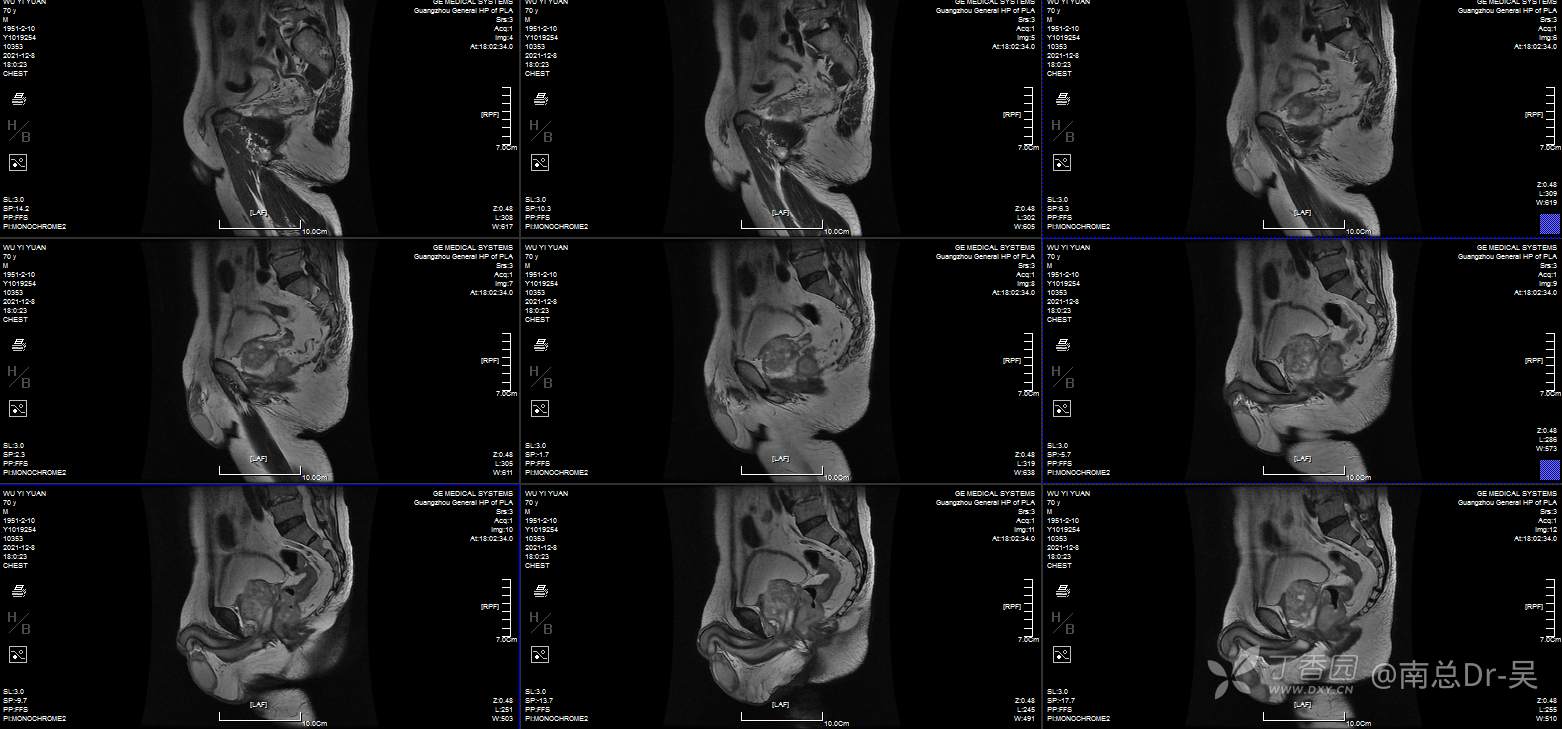

男性患者,81岁,诊断为:超低位直肠癌。肠镜提示距肛门2cm直肠占位,病理:中分化腺癌。患者本人有着强烈的保肛愿望,且评估该患者术前肛门功能良好,因此如何实施高质量的保肛手术是值得关注的问题。

低位直肠癌保肛手术方式多种多样,有ISR、TATME、Bacon、PAKS等等,但每一种手术有着其自身的优劣势,因此合适的手术是保证患者最大获益的前提。

直肠癌经肛拖出适形切除肛门功能重建术是一种两期法的手术,一期先经腹腔镜下直肠癌经肛外翻拖出切除,直视下适形切除肿瘤,尽量保留健侧的肛门括约肌。同时将近端结肠拖出至肛门外约4-6cm,待肠管与肛管自然愈合后约3周,局麻下行肠管切除、肛门整形术。

该手术其实是ISR+NOSES+BACON式的结合及改良,优势为“”“四无一有”腹部无切口、无引流管、无吻合口、无造口、有肛门功能。术后第1天即可恢复进食,符合ERAS理念,后续的辅助治疗可提前,术后5天可出院。

手术的技术要点在于腹腔镜下腹腔组的分离要达到括约肌间平面,肛门组经肛将直肠及肿瘤一起外翻拖出肛外,经肛门直视下适形切除病灶,遵循远切缘大于1cm的原则下,肿瘤侧多切,健侧多保留原则,目的是为多保留肛门括约肌,避免了以往的直线切除的健侧括约肌过多切除,影响术后肛门功能。残存的肛门外括约肌及耻骨直肠肌进行重建修复,重建新的肛直肠角,进一步改善术后肛门功能。近端结肠拖出长度以系膜松弛为原则,目的是为了预防术后早期出现的拖出肠管坏死,这方面技巧日后再说。最后二期的整形切除手术更需技巧,一是多保留粘膜,二是尽量切除增生的纤维瘢痕组织,三是缝合时带部分括约肌,达到缝合结束后粘膜是内翻,肛门外观良好。同时避免术后出现肛门狭窄、粘膜脱垂及少见的直肠漏。